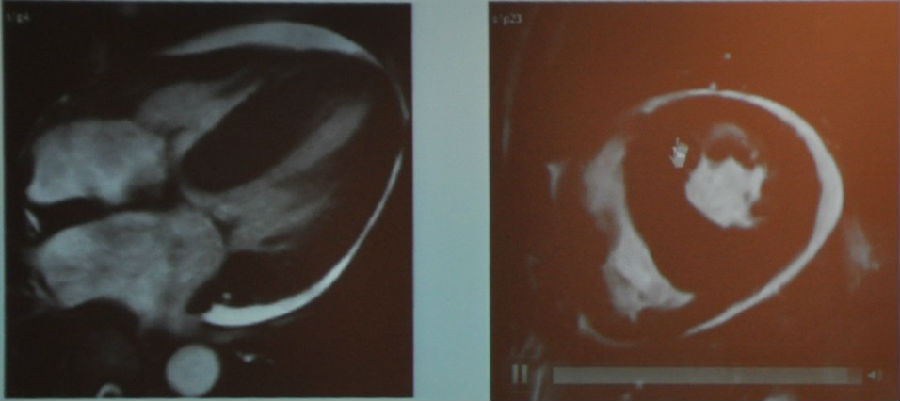

图13 MR成像

患者的心脏收缩功能是完全正常的,但是心包及其肥厚(1cm),从上图中各种成像中都能看到心包像个壳一样包住了心脏,而且心包弥散性纤维化伴局部钙化。

该患者最终被诊断为缩窄性心包炎,紧接着做了心包剥离术。

图14 MR成像

右室、右房严重扩张,伴功能低下。我们从图中可以看到左心已经被挤得很小了。

患者被诊为慢性肺源性心脏病,伴右心衰竭、肺动脉高压。当然这是一个常见病,但是做出明确诊断对患者来说也是非常重要的。